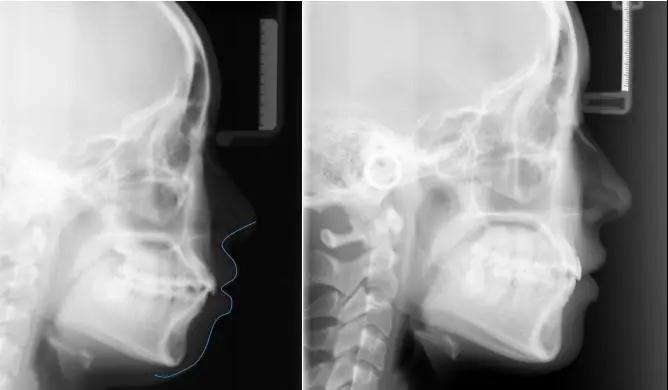

拍X片

下面,就让我们一起来欣赏隐适美牙齿矫正(无托槽矫治)前后对比效果吧:

案例三 :下颌后缩

(诊断 :安氏II类I分类,深覆盖,深覆颌治疗方法 :扩弓,拔除第一前磨牙;矫治器数量 :上颌:41+35=76,下颌:41+35=76;治疗时间 :34个月)